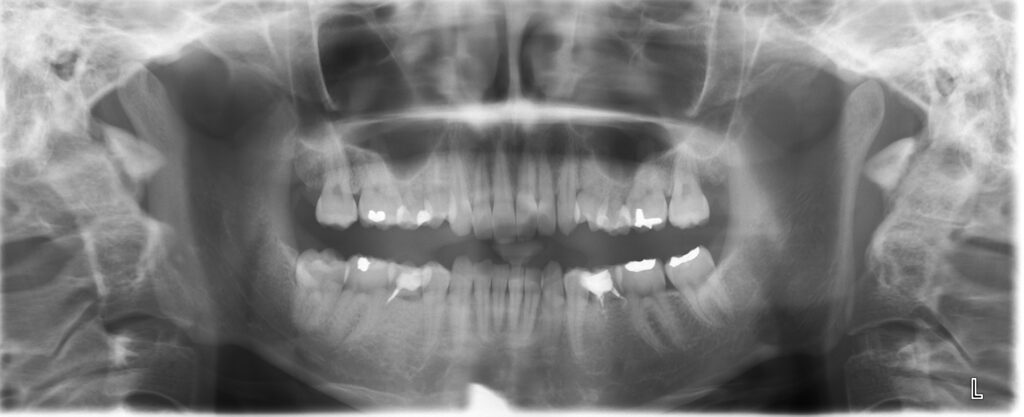

なにより歯列矯正をするにあたって、精密に検査をするとこのような図形が一つの

指標としてでます。

プロフィログラムというものです。

こちらは成人女性の実際の患者さんのものです。

赤い線が成人女性の平均値です。

黒い線がこの方のお顔のバランスということになります。

この青丸の部分が上の前歯、下の前歯の傾斜にあたる部分で

ここでお話しているところの

突出

ということになります。

平均値に比べてかなり前方にありますので

いわゆる出っ歯という状態です。

顎の大きさはさほど平均値と変わりませんから

歯が大きい、スペースがないといえるわけです。